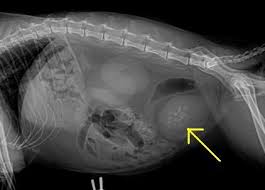

Homevet How Can I Treat My Cat S Cystitis Or Fus Or Flutd

Homevet How Can I Treat My Cat S Cystitis Or Fus Or Flutd from www.homevet.com

Just like humans, kitties can suffer from bladder stones. My cat had ultra sound and vet said there r mineral deposits in bladder and small amount in kidney. The amounts of meat will be increased, as these will make the urine more acidic. Urinalysis showed blood but no crystals. The stones may contain potassium, sodium, calcium or ammonia. Adding extra water to the diet of cats who have had urinary crystals or stones cannot hurt, provided the cat doesn't mind it and is consuming enough of the balanced food to maintain a healthy body weight. Certain cat breeds, such as himalayans, have a genetic predisposition toward developing mineral deposits in the bladder. The scientific term for the development of stones in ay part of the urinary tract is urolithiasis.some breeds are predisposed to the condition, including persian, himalayan and burmese cats.male cats are also more likely to develop problematic kidney stones due to having a narrower ureter, especially those which have been neutered.

Had blood in urine and urinates often and small amounts.